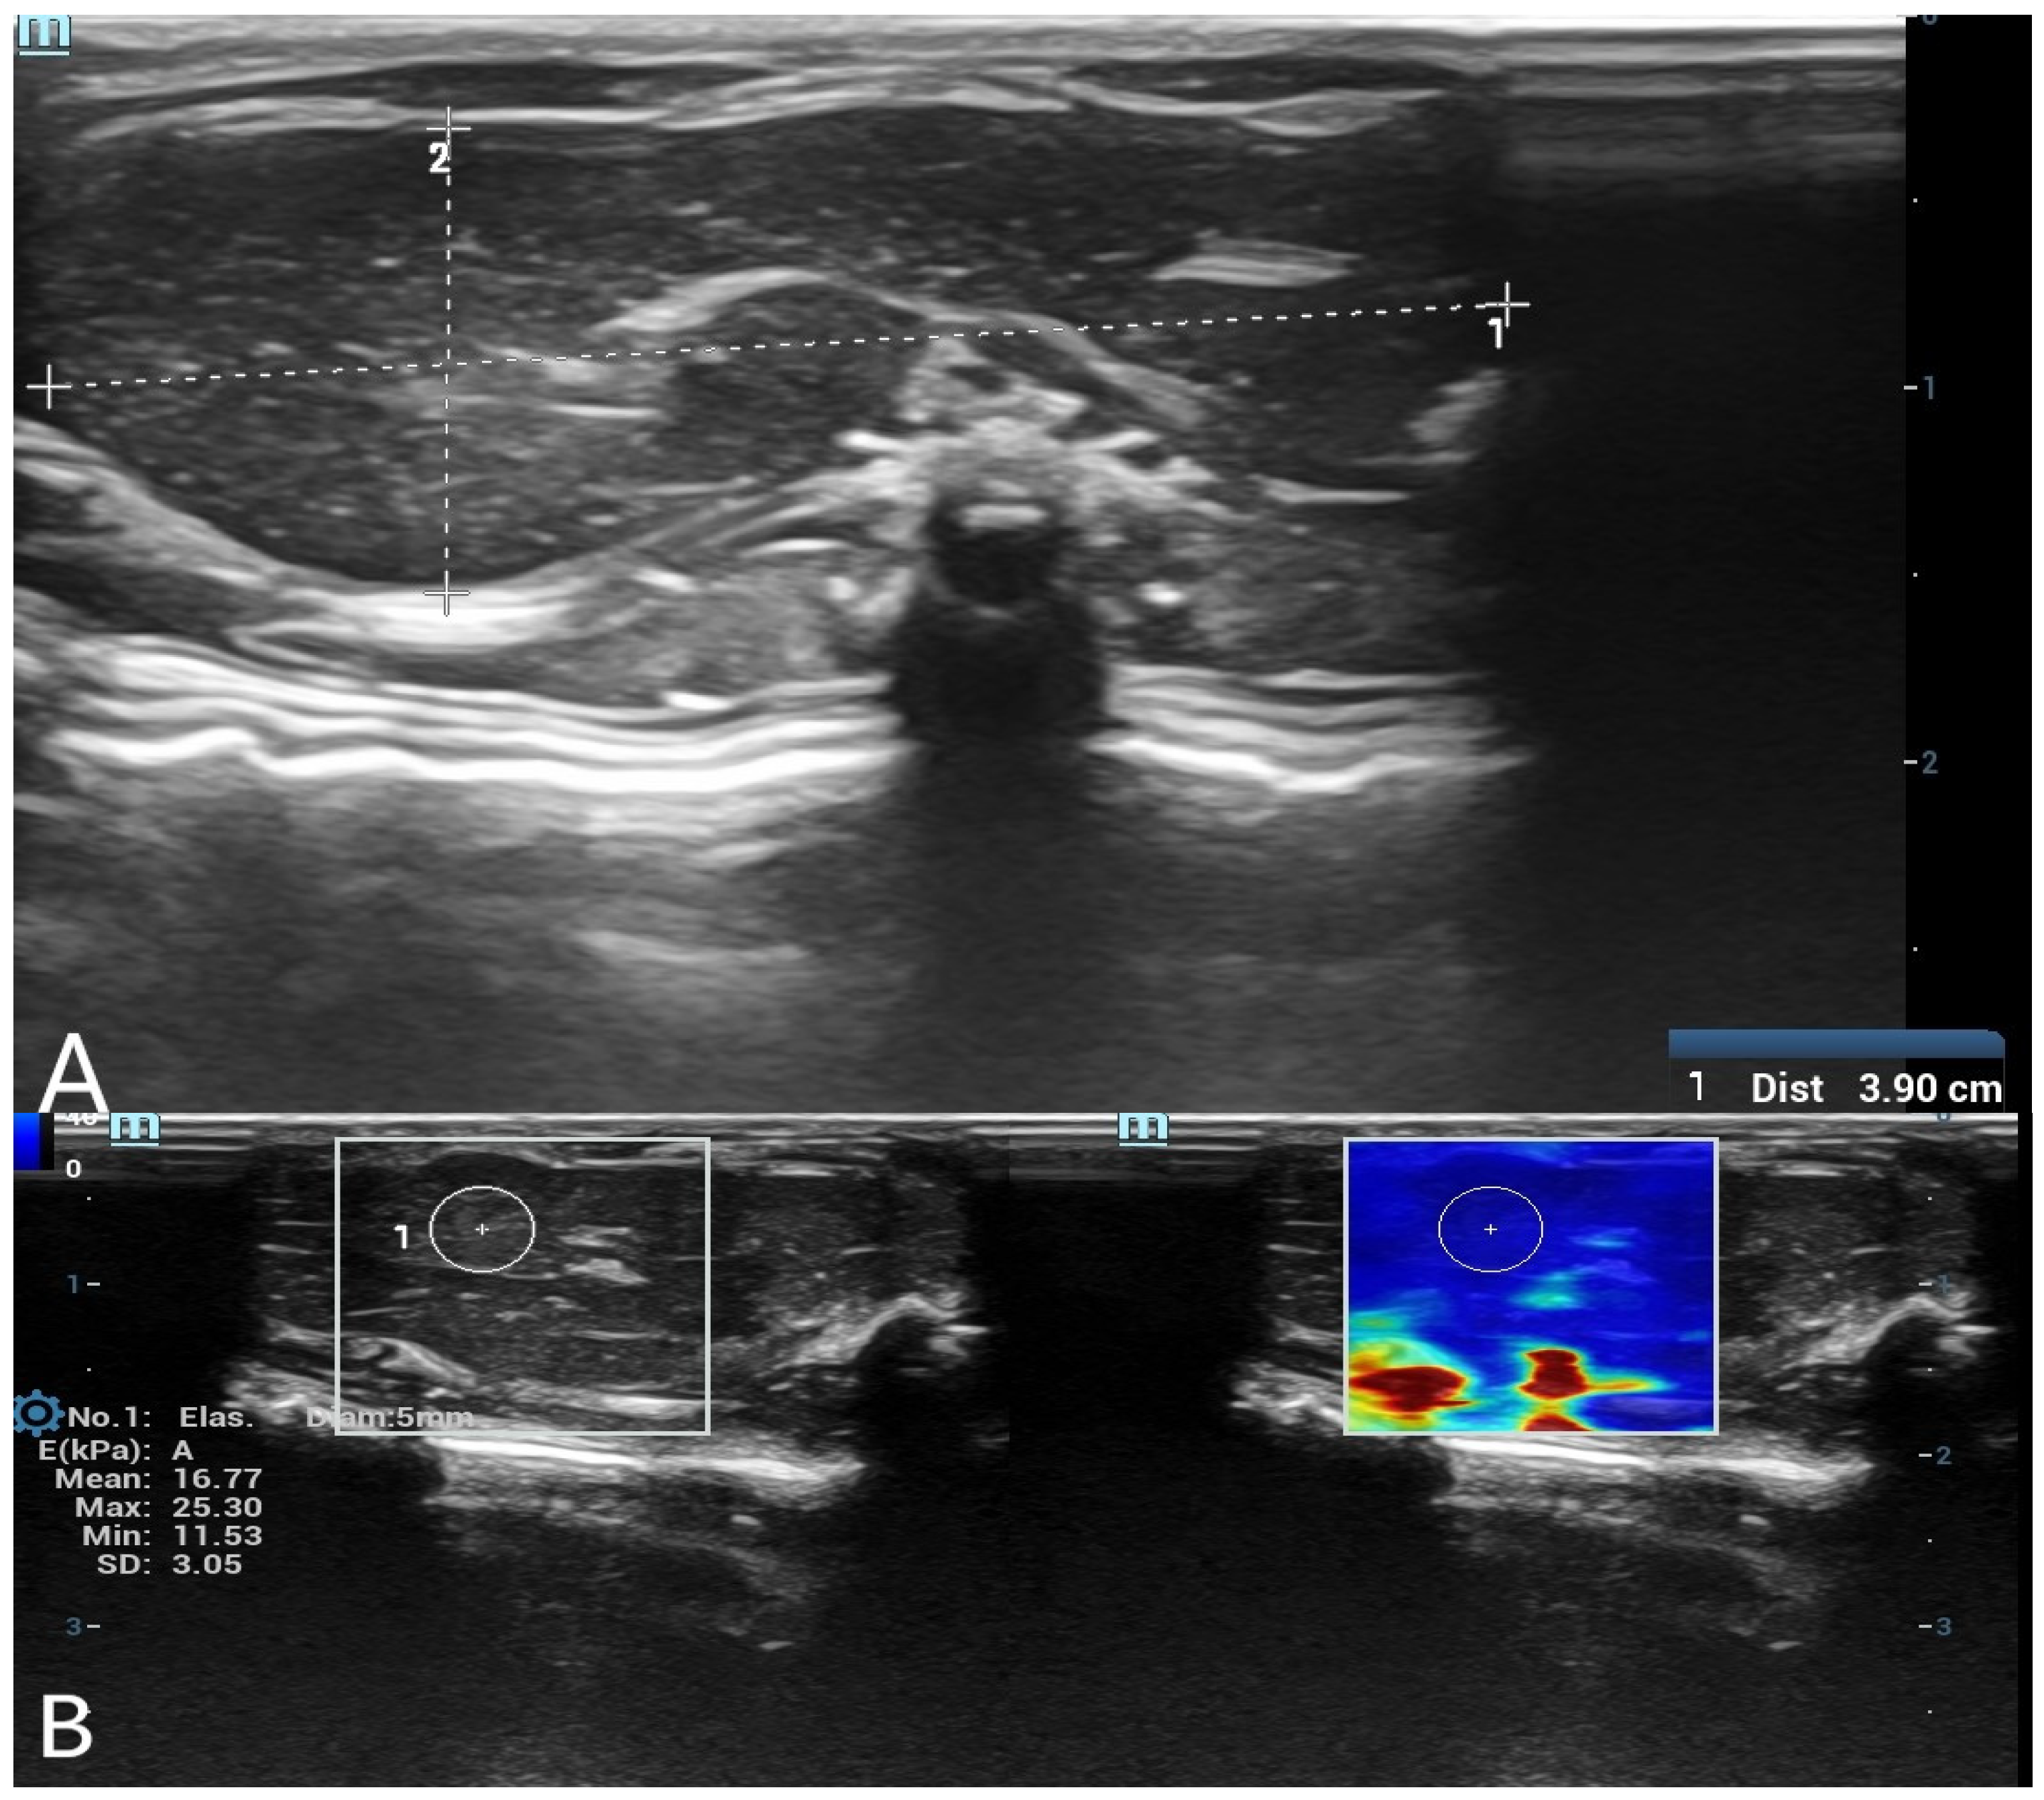

SWE measurements were acquired by a radiologist with over 8 years of experience in ultrasonography. A circular region of interest (ROI) with a diameter of 5 mm was placed centrally within the liver parenchyma, and a 3 mm ROI was used for the spleen parenchyma. ROIs were placed carefully in homogeneous tissue areas, avoiding visible ducts, vessels, or peripheral artifacts. The measurement protocol was standardized based on consensus among three radiologists before the study began. At each time point, three separate measurements were obtained and averaged. Only SWE maps without significant artifacts were included in the analysis. SWE results were recorded in kilopascals (kPa), and minimum, maximum, mean, and standard deviation (SD) values were calculated for each organ (Figure 1 and Figure 2).

Figure 1. (A) B-mode ultrasound measurement of liver long and short diameters. A grayscale ultrasound image showing the measurement of liver long and short diameters. The calipers indicate the dimensions of the liver in the postmortem assessment. (B) Shear wave elastography (SWE) measurement of liver stiffness with a 5 mm region of interest (ROI). The left panel displays the grayscale ultrasound image of the liver, while the right panel shows the corresponding SWE color map. A 5 mm circular ROI is placed in the liver parenchyma to obtain quantitative stiffness values in kilopascals (kPa).